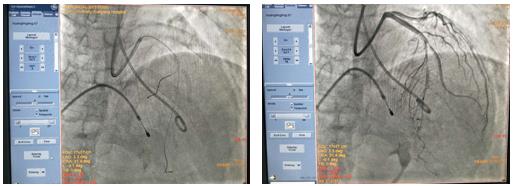

經(jīng)過(guò)反復(fù)討論后,吳棟梁主任醫(yī)師作為手術(shù)指導(dǎo)者,在崔旭輝主任醫(yī)師團(tuán)隊(duì)操作下,最終決定在臨時(shí)起搏器保護(hù)下行冠狀動(dòng)脈造影術(shù)及心臟化學(xué)消融術(shù)。術(shù)中通過(guò)造影確認(rèn)第二穿隔支未消融靶血管,測(cè)壓顯示左室壓222/13mmHg,主動(dòng)脈壓136/88 mmHg,壓力階差86mmHg。經(jīng)SPRINTER OTW球囊緩慢注入無(wú)水酒精0.8ml,10分鐘后復(fù)測(cè)左心室及主動(dòng)脈壓分別為162/12 mmHg、123/82 mmHg,術(shù)后第5天,患者未訴胸悶、氣短、心悸等不適,復(fù)查心臟彩超示:EF:63%,F(xiàn)S:34%,收縮期左室流出道血流速度增快,Vmax:436cm/s,PG:76mmHg,二尖瓣反流長(zhǎng)度5.7cm,面積7.4cm2,三尖瓣反流長(zhǎng)度2.3cm,面積1.8cm2;室間隔中上段聲像圖所見,多考慮為肥厚型心肌病伴左室流出道梗阻;二尖瓣關(guān)閉不全(相對(duì)性);左房大;左室收縮功能正常,舒張功能減低;彩色血流示:左室流出道湍流,較前速度略減低;二尖瓣反流(中量)、三尖瓣反流(少量),明顯改善了患者癥狀。